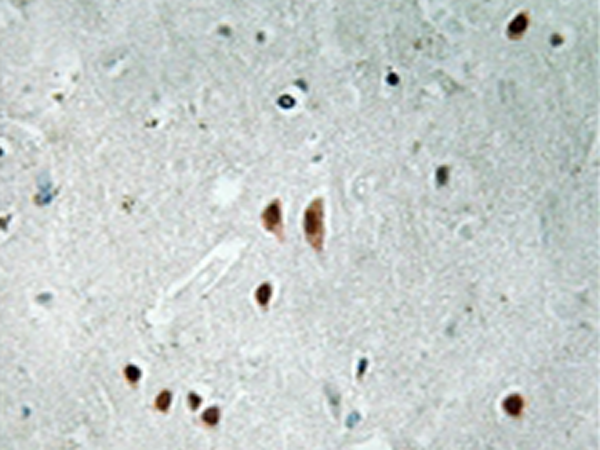

IHC positive control: |

Human brain tissue |